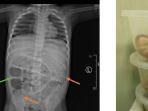

Dokter Kaget Setelah Lihat Isi Perut Bocah yang Membesar, Tak Bisa BAB Seminggu

Dokter menemukan hal mengejutkan saat mengoperasi perut seorang bocah laki-laki berusia 3 tahun di RSD dr Soebandi Jember.